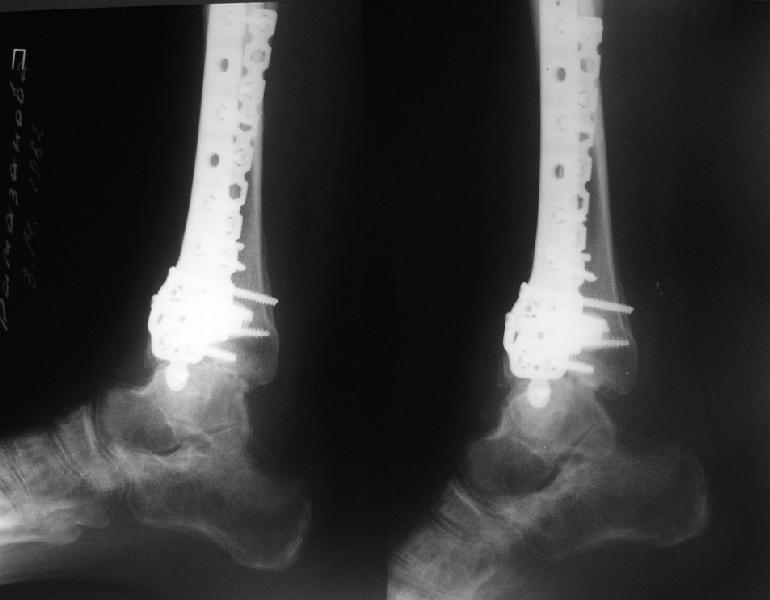

Dear коллеги,Обратилась женщина, 25 л. 8 мес. назад в одной из больниц сделан остеосинтез пилона. На сегодня ходит без дополнительной опоры, хромая на поврежденную ногу. Движения в голеностопном суставе еще есть. Снимки в приложении.

A female, 25, 8 month ago operated elsewhere. To date walks without support with pain and limp. The ankle is mobile yet. Images attached.The question is what to do now? The patient is not very keen on ankle fusion (though likely could change her mind if necessary)Is it worth to try a reconstruction procedure and what kind? Maybe it allows to restore alignment and tibio-fibular relationship - will it provide painless limb for more or less significant time?Or just remove the hardware and leave her alone until she herself comes for fusion?

She has an intraarticular screw on CT, best is to remove all and wait untill she asks for fusion.

CT images/xrays confirm incongruity of articular surfaces as well as intraarticular screws.

removing just those screws which have penetrated the joint may take some pain away.

Александр, добрый вечер! К сожалению, боюсь, что, кроме артродеза, ничего не осталось, упущено время. Просто убрать железо конечно можно, а куда деть вальгусную установку, "синдесмоз", признаки артрофиброза, которые прослеживаются на представленных рентгенограммах. Вопрос же стоит в качестве жизни пациентки, может ей тактично все объяснить, что чем дольше она будет так ходить, тем возможно болевой синдром будет более стойким и усилится деформация.